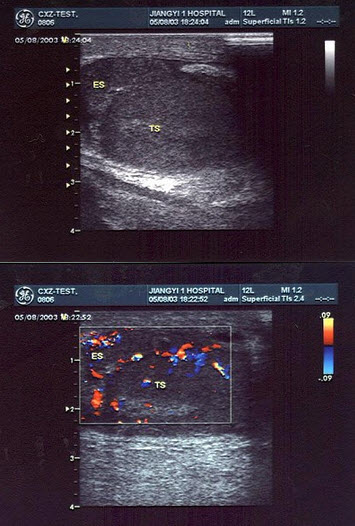

17、单项选择题

患者发现颈部肿块两年,无明显不适。甲状腺超声见甲状腺肿大回声不均匀,如图。最可能的诊断为()